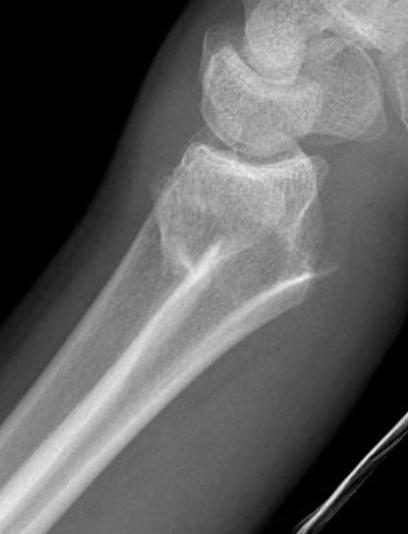

Colle's Fracture

- distal radial fracture with dorsal displacement

All fractures should be reduced initially and reassessed

- conscious sedation

- 2 minutes of traction / reduction of deformity

- backslab / elevation in gallows

- re-xray

CT for further evaluation of articular congruency